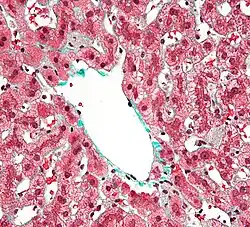

Células de Kupffer são células que recobrem, junto com as células endoteliais típicas, as placas hepatocelulares. São capazes de fagocitar substâncias estranhas presentes no sangue dos seios hepáticos, sangue esse que chega até aos sinusóides pela veia porta. Possui muitos lisossomas para cumprir sua função como célula fagocitária e um núcleo grande e oval. É envolto por fibras reticulares. São células descontínuas e permitem a passagem do plasma aos hepatócitos.

São macrófagos encontrados na superfície luminal das células endoteliais, cujas principais funções são: metabolizar eritrócitos velhos, digerir hemoglobina, secretar proteínas relacionadas com os processos imunólogicos e destruir bactérias que eventualmente penetrem no sangue portal a partir do intestino grosso, cuja proporção celular no fígado chega a 15%.